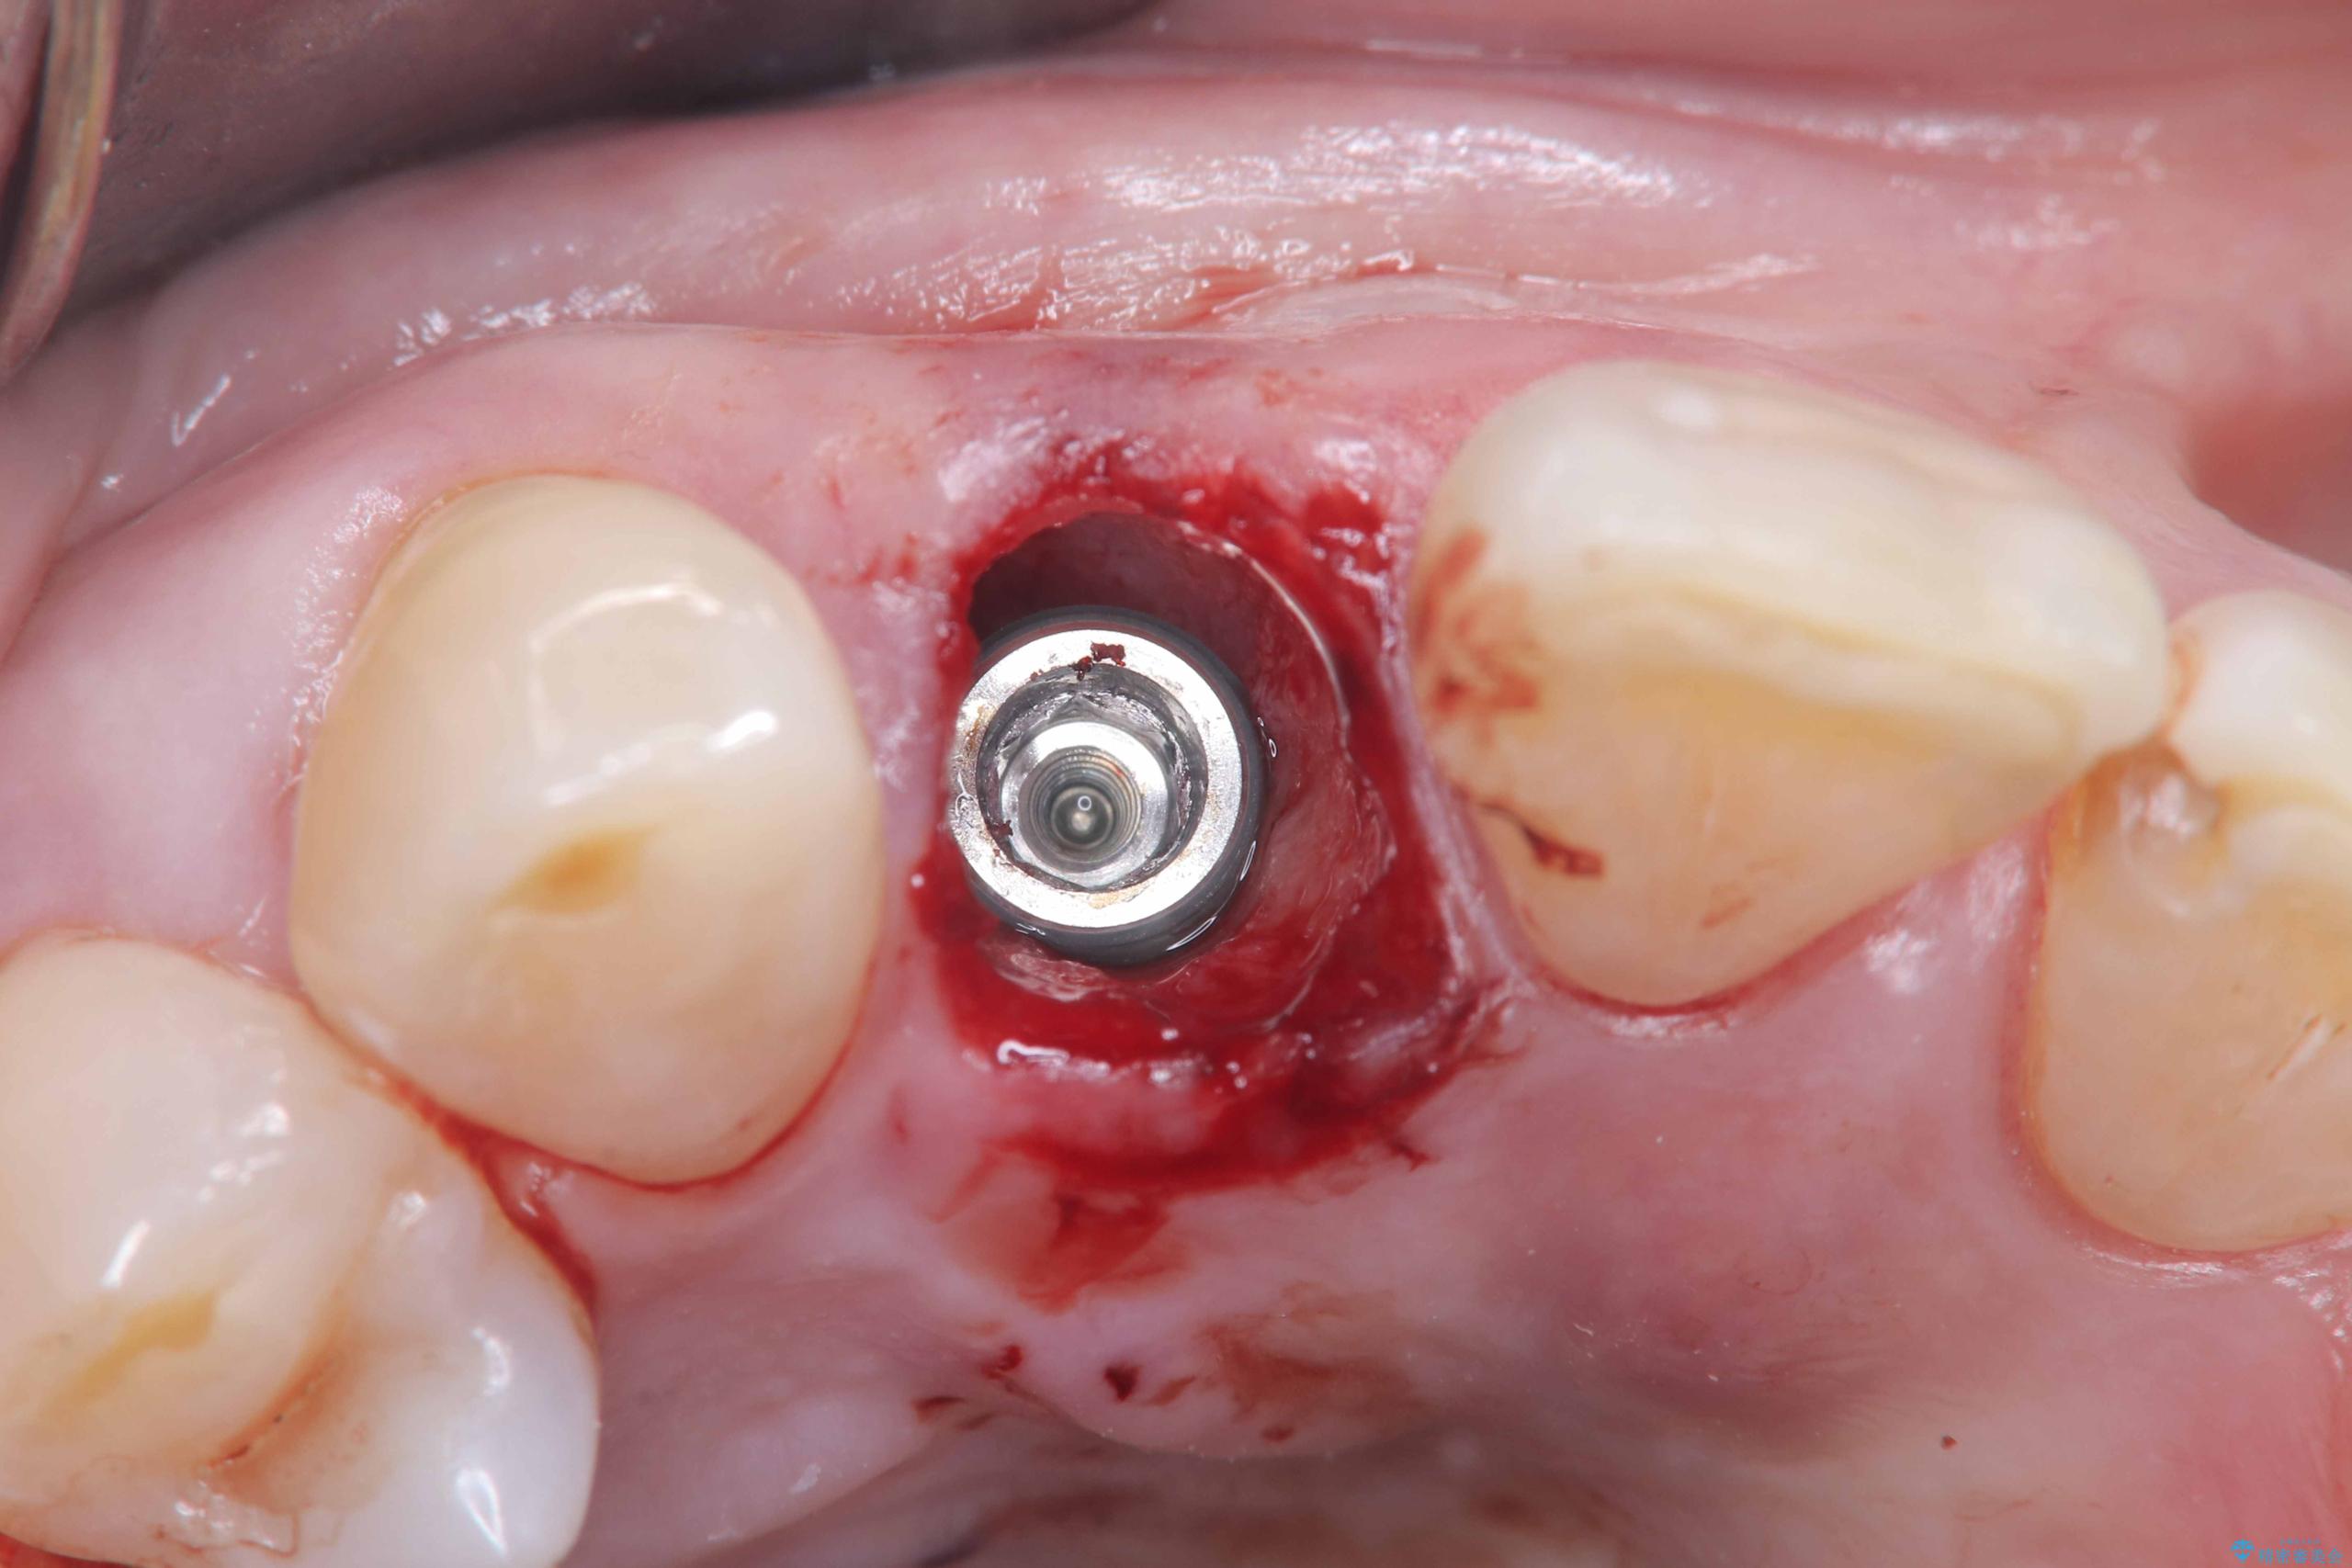

インプラント治療は、低侵襲で短期間に行える「抜歯即時インプラント治療」を選択しました。

この方法は、抜歯したその日にインプラントを埋入し、手術が1回で済むのが大きな特徴です。

治療期間も短く、抜歯からわずか3か月でオールセラミッククラウンを装着することができます。

また、オペ当日には仮歯まで装着するため、見た目を気にせず普段通りの生活を送ることができます。